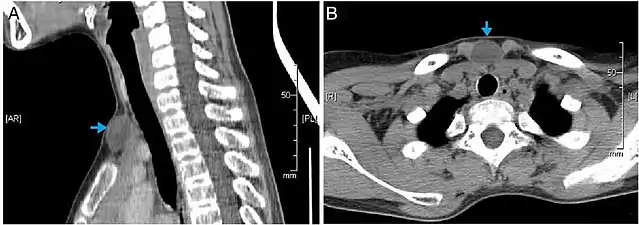

Scanner montrant une image hypodense homogène (kystenon spécifique)